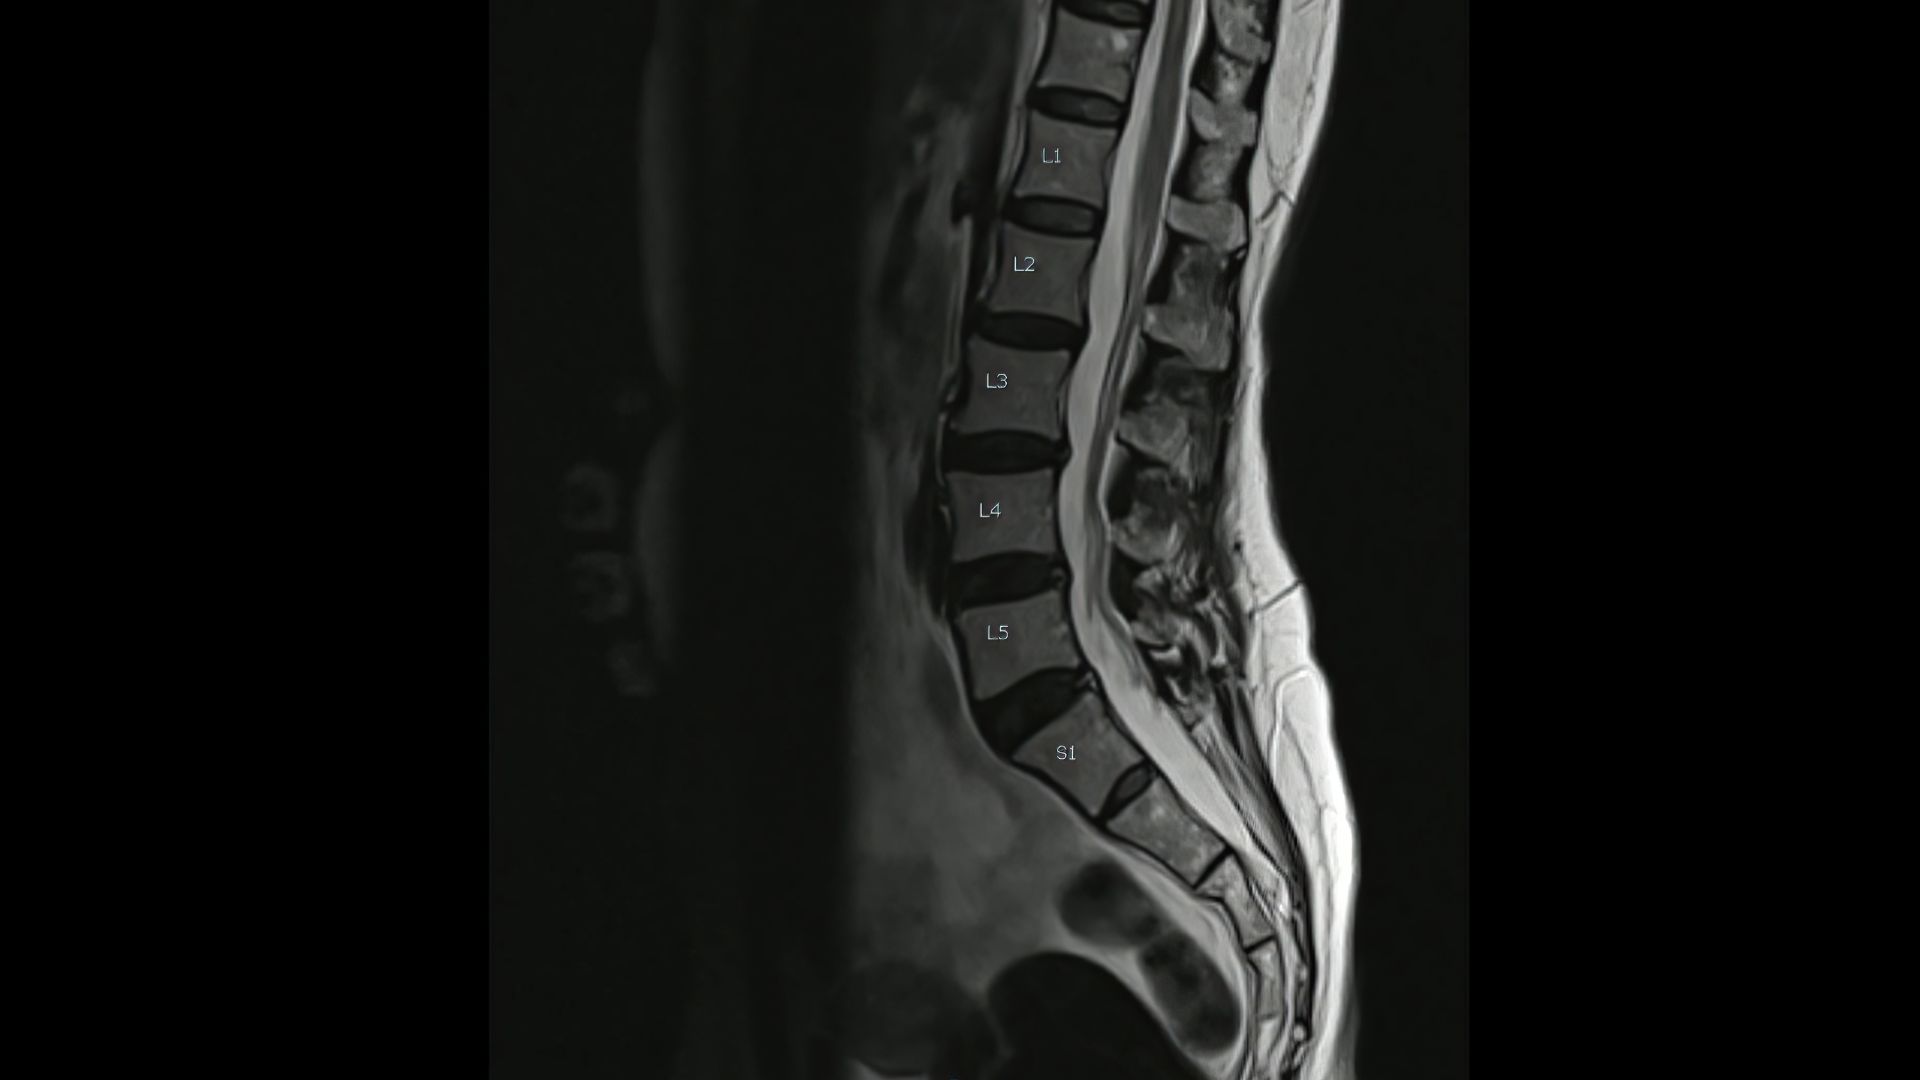

La columna lumbar consta de 5 vèrtebres mòbils en disposició lordòtica (quan la columna fa una corba cap endins a la part baixa de l’esquena) amb 5 parells d’arrels nervioses. Els ossos sacre i coxis consten cadascun de 5 vèrtebres fusionades.

L’envelliment de la columna lumbar condiciona un estretament de l’espai per on transcorren els elements neurals (arrels nervioses), produint-se principalment a nivell central però també en els recessos laterals (espais a dreta i esquerra de la columna per on passen elements del sistema nerviós) i foramens vertebrals (forat a l'interior de la columna per on passen elements del sistema nerviós).